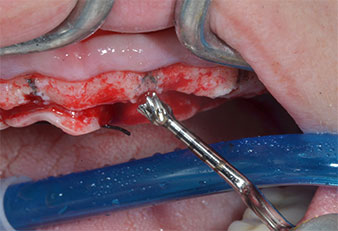

Ein flammenförmiges, diamantiertes piezochirurgisches Instrument (Piezomed I1) wurde verwendet, um die Implantatpositionen zu markieren und die Pilotpräparationen durchzuführen (Abb. 3). Dabei wurde darauf geachtet, eine Auf- und Abbewegung mit reduzierter Leistung, voller Spülung und niedrigem Druck (unter 300 g) anzuwenden. Als Nächstes wurde ein Pilotinstrument (Piezomed I2A/I2P) zur initialen Erweiterung der Implantatlager auf einen Durchmesser von 2 mm verwendet (Abb. 4), gefolgt von einem 3-mm-Instrument (Abb. 5).